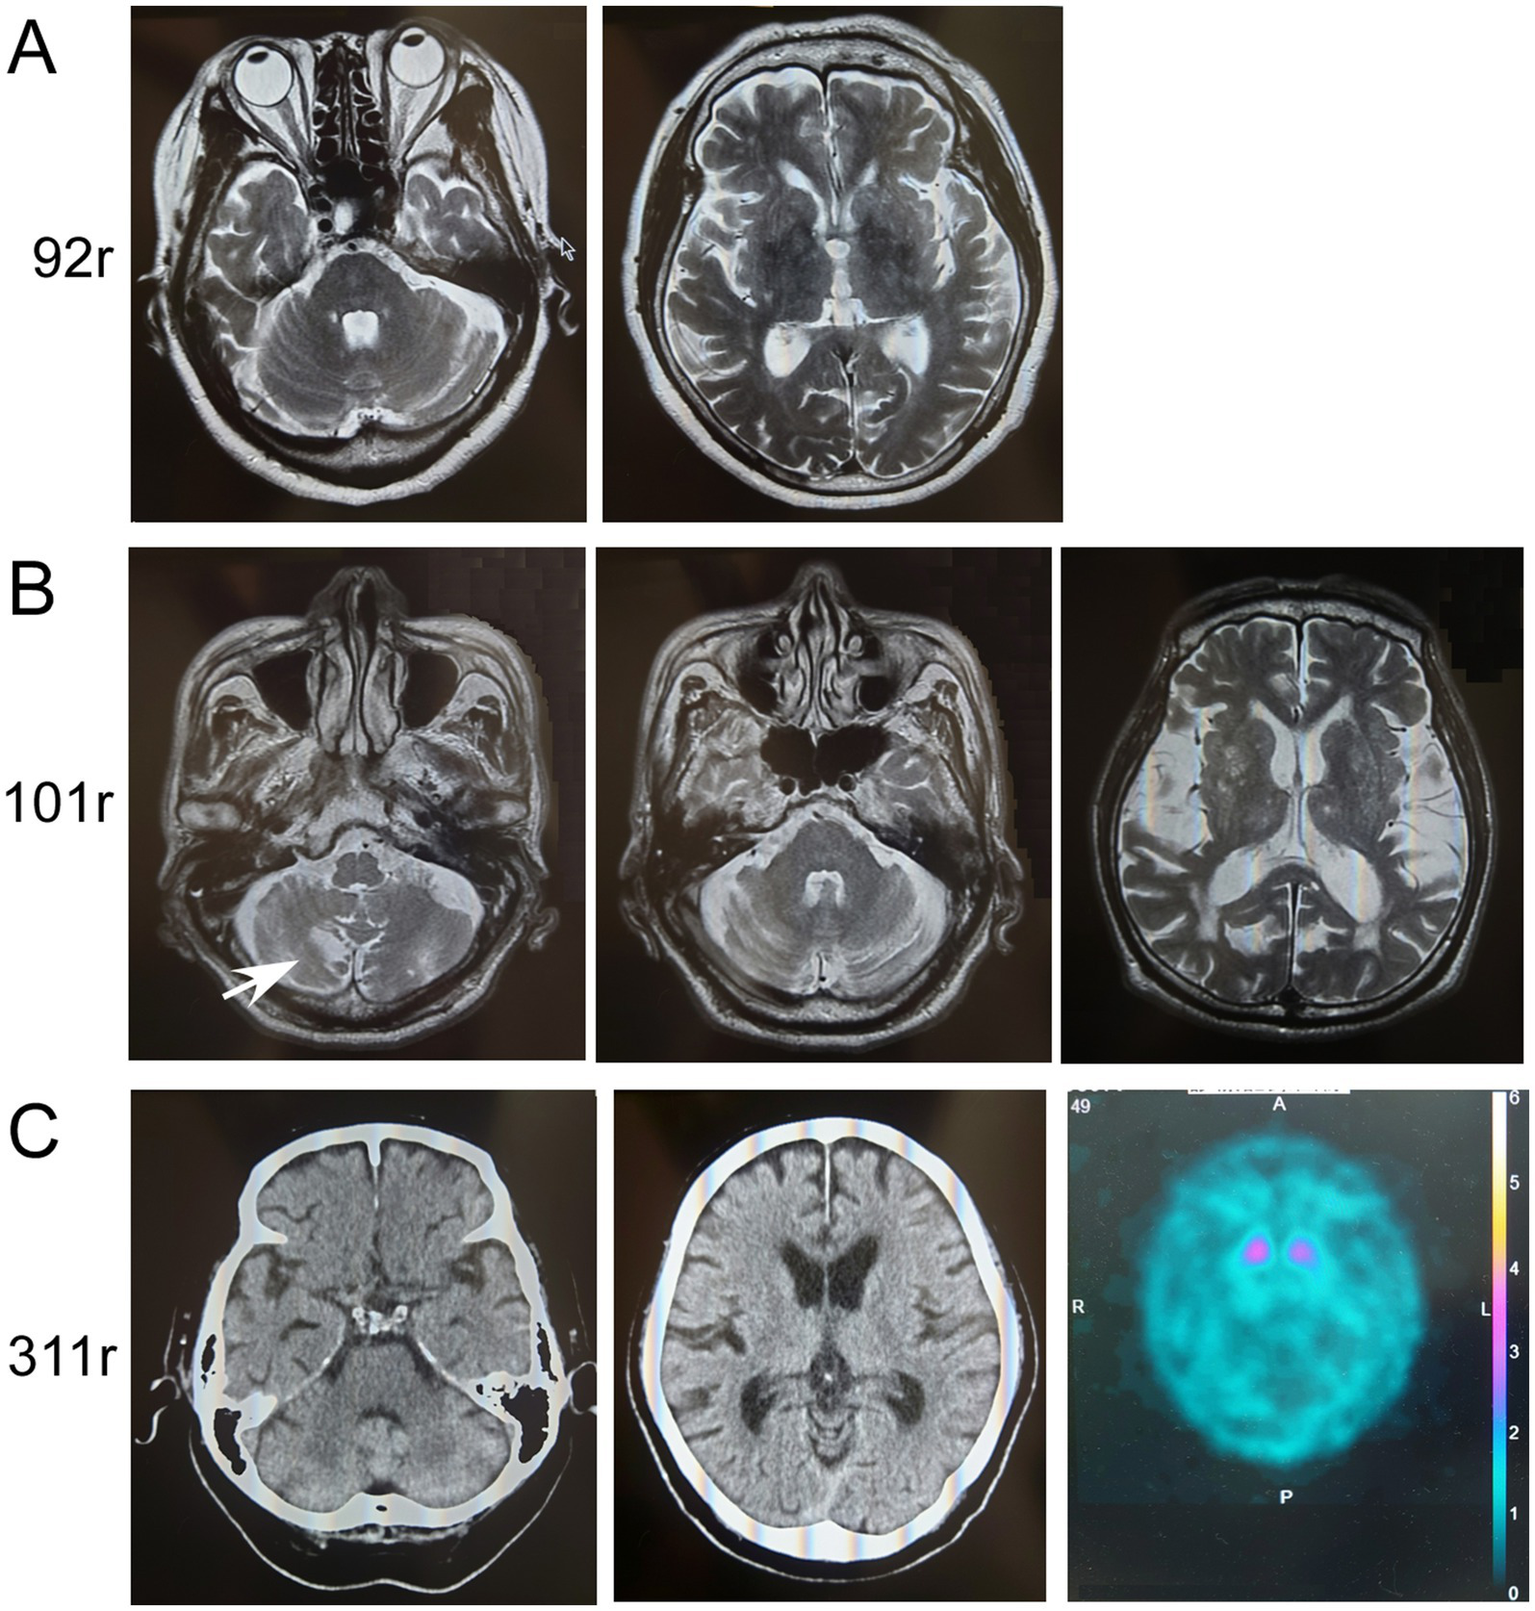

Clinical information about patients with ATXN8OS mutations

The clinical information of the three patients with ATXN8OS mutations in this study, along with previously reported patients, is summarized in Table 1 (14, 15). Our patients responded well to levodopa or the dopamine agonist rotigotine. They seemed to have typical PD symptoms. According to the reported study (32), the phenotypes of our patients were as follows: Patients 1 and 3 were akinetic-rigid type, and Patient 2 was mixed type (Table 1). No patient had cerebellar ataxia. Imaging findings of the three patients with ATXN8OS mutations are shown in Figure 3. Patient 1, with 92 repeats, had no obvious abnormality on MRI. Patient 2 with 101 repeats had an asymptomatic cerebellar infarction with non-specific atrophy in the cerebrum and cerebellum (Figure 3B). Patient 3, with 311 repeats in ATXN8OS, had no obvious abnormality on MRI but showed reduced striatal dopaminergic transporter uptake (Figure 3C). Other patients did not undergo dopaminergic transporter imaging or other functional imaging studies. All patients with ATXN8OS mutations reported swallowing difficulties or discomfort in the throat after eating, which was supported by videofluoroscopic results (Figure 4). Patient 1 exhibited aspiration (Figure 4A), and Patients 2 and 3 exhibited laryngeal penetration (Figs. 4B,C). No correlation was found between the number of repeats and severity or age at onset because the sample size was too small for statistical analysis.

Figure 3

Imaging results of patients with ATXN8OS repeat expansions. (A) MRI of Patient 1 with 92 repeats (92r) showed no apparent atrophy of the cerebellum (upper panel) or cerebrum (lower panel). (B) MRI of Patient 2 with 101 repeats (101r) showed asymptomatic infarction of the cerebellum (arrow) and slight non-specific atrophy of the cerebellum or mild atrophy of the cerebrum with chronic ischemic lesions. (C) Computed tomography (CT) of the head in Patient 3 with 311 repeats (311r) showed no apparent atrophy of the cerebellum (left panel) or cerebrum (right panel). Dopamine-transporter single photon emission computed tomography showed marked reduction of the uptakes in the striatum. The specific binding ratio was 1.26 on the right striatum and 1.62 on the left.

Imaging results, especially functional imaging, have been rarely reported in patients with non-coding repeat expansions. Dopamine-transporter single photon emission computed tomography in this study showed a marked reduction of striatal uptake, a cardinal feature of PD. MRI revealed no apparent atrophy of the cerebellum in the three patients with ATXN8OS mutations. This is compatible with the reported findings of ATXN8OS-related PD (6). Similarly, RFC1-related PD showed no apparent atrophy in the cerebellum. A patient with RFC1 repeat expansions a year after onset had an apparently normal H/M ratio in MIBG scintigraphy, which was supposed to be reduced in PD. However, H/M ratios are sometimes within normal ranges during the early phase of PD (2). In contrast, the increased washout ratio observed here was compatible with that in PD (38). These findings suggest that imaging findings in PD associated with non-coding repeat expansions are indistinguishable from those without repeat expansions.